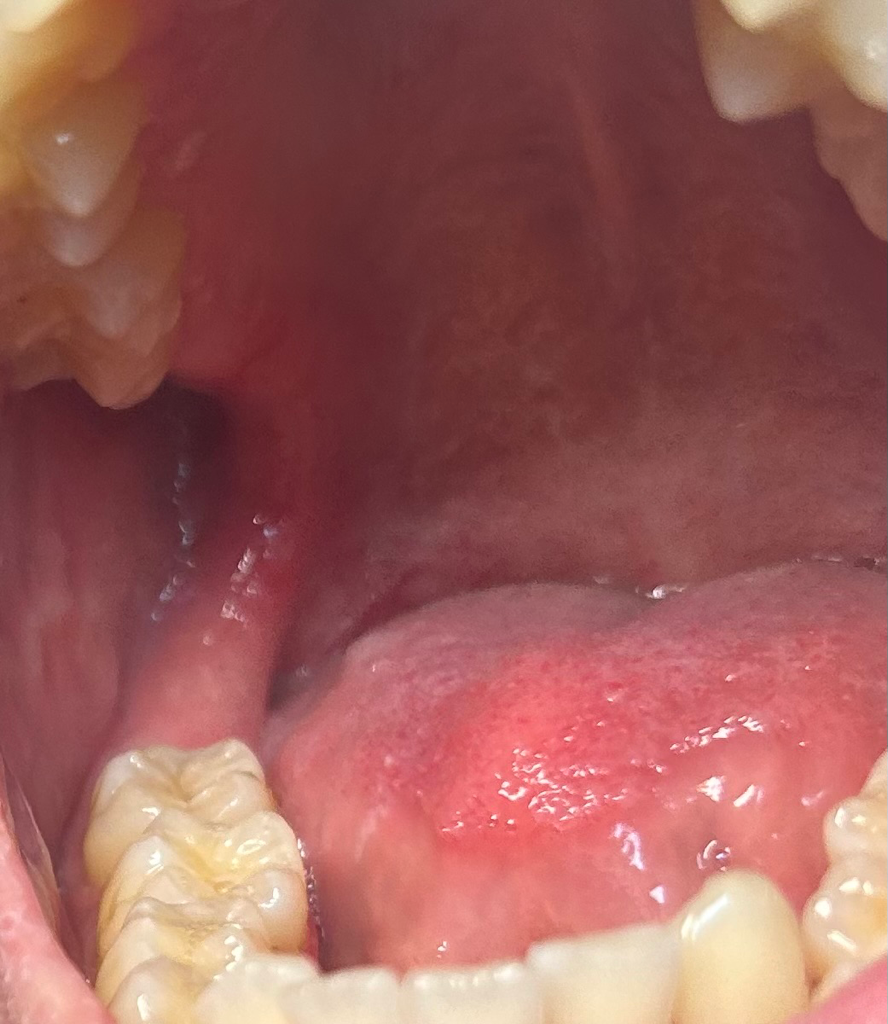

일단 구강암은 아닌것으로 보입니다.

구강과 혀 전반에 걸쳐 퍼져있는 병소가 만약에 암이라면 이미 말기암 일것임으로 말이 되지 않습니다.

거의 정상으로 보입니다만.

단수히 물집이 잡히신거 같습니다. 크게 문제가 잇는건 아니니 너무 걱정하지않으셔도 될것같습니다. 구내염증상이신거 같습니다 .

구강내 점막은 자극을 받거나 하면 점막에 변화가 생기기도 합니다.

구강암의 가능성은 매우 작지만 걱정이 되신다면 치과엣 진료를 받아 보는것이 좋습니다.